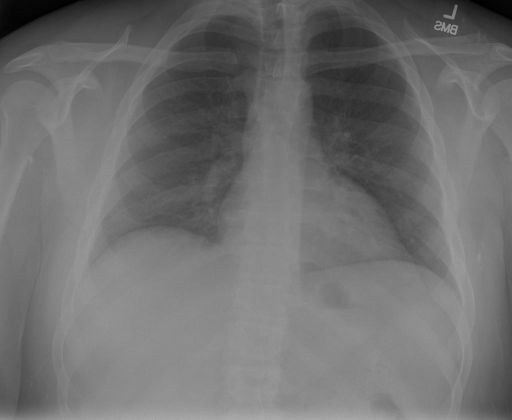

## 本文贡献 ![](./assets/images/xrayglm.png) - 借助ChatGPT以及公开的数据集,我们构造了一个`X光影像-诊断报告`对的医学多模态数据集; - 我们将构建的中文胸部X光片诊断数据集在[VisualGLM-6B](https://github.com/THUDM/VisualGLM-6B)进行微调训练,并开放了部分训练权重用于学术研究; ## 数据集 - [MIMIC-CXR](https://physionet.org/content/mimic-cxr-jpg/2.0.0/)是一个公开可用的胸部X光片数据集,包括377,110张图像和227,827个相关报告。 - [OpenI](https://openi.nlm.nih.gov/faq#collection)是一个来自印第安纳大学医院的胸部X光片数据集,包括6,459张图像和3,955个报告。 在上述工作中,报告信息都为非结构化的,不利于科学研究。为了生成合理的医学报告,我们对两个数据集进行了预处理,并最终得到了可以用于训练的**英文报告**。除此之外,为了更好的支持中文社区发展,借助ChatGPT的能力,我们将英文报告进行了中文翻译,并最终形成了可用于训练的数据集。 |数据集|数量|下载链接| |:-|:-|:-| |MIMIC-CXR-zh|-|-| |OpenI-zh|6,423|[诊疗报告(英文)](./data/openi-en.json)、[诊疗报告(中文)](./data/Xray/openi-zh.json) 、[X光影像](https://pan.baidu.com/s/13GBsDMKf6xBZBSHpoWH_EA?pwd=k9sh)| ## 快速上手 1. 安装环境 ```bash # 安装依赖 pip install -r requirements.txt # 国内换源安装依赖 pip install -i https://mirrors.aliyun.com/pypi/simple/ -r requirements.txt ``` 此时默认会安装`deepspeed`库(支持`sat`库训练),此库对于模型推理并非必要,同时部分`Windows`环境安装此库时会遇到问题。 如果想绕过`deepspeed`安装,我们可以将命令改为: ```bash # 安装依赖 pip install -i https://mirrors.aliyun.com/pypi/simple/ -r requirements_wo_ds.txt # 安装SwissArmyTransformer pip install -i https://mirrors.aliyun.com/pypi/simple/ --no-deps "SwissArmyTransformer>=0.3.6" ``` 2. 模型推理 |模型权重|下载链接| |:-|:-| |checkpoints-XrayGLM-300|-| |checkpoints-XrayGLM-3000|-| CLI推理: ```python python cli_demo.py --from_pretrained checkpoints/checkpoints-XrayGLM-3000 --prompt_zh '详细描述这张胸部X光片的诊断结果' ``` 更多[参数](https://github.com/WangRongsheng/XrayGLM/blob/main/cli_demo.py#L16) ## 效果展示 影像诊断: |X光影像|诊疗报告(医生)|XrayGLM| |:-|:-|:-| |![](./data/Xray/2_1.png)|根据X射线图像,心脏大小正常,肺部看起来很清晰。已经排除了肺炎、积液、水肿、气胸、腺病、结节或肿块的存在。该发现表明一切正常。换句话说,总体印象是胸部正常。|X光片显示,心脏大小正常。肺部没有气胸或胸腔积液的证据。骨骼结构看起来没有任何异常。总的来说,X光片表明没有发现急性心肺疾病的迹象。| |![](./data/Xray/2882_1.png)|X光图片显示没有扭曲的区域、可疑的骨质不透明度或胸腺积液。心脏大小轻微增大,但非常稳定。此外,没有气胸的证据,肺野也正常。总体来说,X光片显示没有急性心脏异常,但要注意轻微的心脏扩大。|X光片显示,心脏大小正常。肺部和纵隔轮廓清晰,没有气胸或胸腔积液的证据。骨骼结构完整,没有任何急性异常。| |![](./data/Xray/2577_1.png)|心影形态在正常范围内。没有急性骨质异常。有可能出现没有明显的吸水或肺实质状况的线索。没有大面积积液或气胸。有可能怀疑其有误吸或肺实质问题。为了确诊和治疗,可能需要进行适当的影像学随访。|心脏大小正常,肺部和纵隔轮廓清晰。没有急性异常或活动受限的证据。没有任何明显的气胸、胸腔积液或肺不张的迹象。此外,也没有发现任何局灶性骨质异常或其他急性疾病。| 多轮对话: |X光影像|诊疗报告(医生)| |:-|:-| |![](./data/Xray/861_1.png)|右侧主动脉突出观察到。心脏大小正常。胸部未发现明显的肺气肿、胸膜积液或可疑的肺部病变。报告指出已知右侧主动脉情况正常。| ```bash >> X光影像路径:./data/Xray/861_1.png >> 用户:这是一张什么图? >> XrayGLM:这张图片显示的是一张肺部检查的X光片。 >> 用户:请描述这张胸部X光片的诊断结果 >> XrayGLM:心脏大小正常,肺部清晰。没有急性心肺疾病的证据。 >> 用户:是否存在肺气肿? >> XrayGLM:没有肺气肿。心脏大小正常,肺部清晰。没有发现急性心肺疾病的证据。 >> 用户:平时饮食该注意什么? >> XrayGLM:饮食应该健康,均衡。建议增加蛋白质的摄入量,因为蛋白质有助于维持肌肉和骨骼的健康。多食用蔬菜、水果、全谷物以及健康的脂肪来源如橄榄油、鱼类等可以帮助获得足够的维生素和矿物质。此外,避免过度饮酒或吸烟,这些习惯可能会对心脏健康产生负面影响。 ``` ## 未来展望 1. 模型的能力更多来源于数据的支持,`OpenI-zh`作为微调数据集,其数据量足以支持研究,在更广泛的任务和性能表现上,我们认为**在大规模数据集上预训练并在高质量少量数据集上微调是一种可行的方案**; 2. 普遍意义的理解上,视觉多模态模型=视觉模型+语言模型。除了需要关注视觉模型信息与语言模型输出的搭配外,还需要**额外关注到语言模型的加强,在人机的对话中,尤其是医疗语言模型的问答上,除了专业的医疗问题回答,带有人文情怀的有温度的回答更应该是我们追寻的目标**。 ## 项目致谢 1. [VisualGLM-6B](https://github.com/THUDM/VisualGLM-6B)为我们提供了基础的代码参考和实现; 2. [MiniGPT-4](https://github.com/Vision-CAIR/MiniGPT-4)为我们这个项目提供了研发思路; 3. ChatGPT生成了高质量的中文版X光检查报告以支持XrayGLM训练; 4. [gpt_academic](https://github.com/binary-husky/gpt_academic)为文档翻译提供了多线程加速; 5. [MedCLIP](https://github.com/RyanWangZf/MedCLIP) 、[BLIP2](https://huggingface.co/docs/transformers/main/model_doc/blip-2) 、[XrayGPT](https://github.com/mbzuai-oryx/XrayGPT) 等工作也有重大的参考意义; ![](./assets/images/mpu.png) 这项工作由[澳门理工大学应用科学学院](https://www.mpu.edu.mo/esca/zh/index.php)硕士生[王荣胜](https://github.com/WangRongsheng) 、[段耀菲](https://github.com/IsBaSO4) 、[李俊蓉](https://github.com/lijunrong0815)完成,指导老师为檀韬副教授、[彭祥佑](http://www.patrickpang.net/)老师。 *特别鸣谢:[USTC-PhD Yongle Luo](https://github.com/kaixindelele) 提供了有3000美金的OpenAI账号,帮助我们完成大量的X光报告翻译工作 ## 免责声明 本项目相关资源仅供学术研究之用,严禁用于商业用途。使用涉及第三方代码的部分时,请严格遵循相应的开源协议。模型生成的内容受模型计算、随机性和量化精度损失等因素影响,本项目无法对其准确性作出保证。即使本项目模型输出符合医学事实,也不能被用作实际医学诊断的依据。对于模型输出的任何内容,本项目不承担任何法律责任,亦不对因使用相关资源和输出结果而可能产生的任何损失承担责任。 ## 项目引用 如果你使用了本项目的模型,数据或者代码,请声明引用: ```bash @misc{wang2023XrayGLM, title={XrayGLM: The first Chinese Medical Multimodal Model that Chest Radiographs Summarization}, author={Rongsheng Wang, Yaofei Duan, Junrong Li, Patrick Pang and Tao Tan}, year={2023}, publisher = {GitHub}, journal = {GitHub repository}, howpublished = {\url{https://github.com/WangRongsheng/XrayGLM}}, } ``` ## 使用许可 此存储库遵循[CC BY-NC-SA](https://creativecommons.org/licenses/by-nc-sa/4.0/) ,请参阅许可条款。